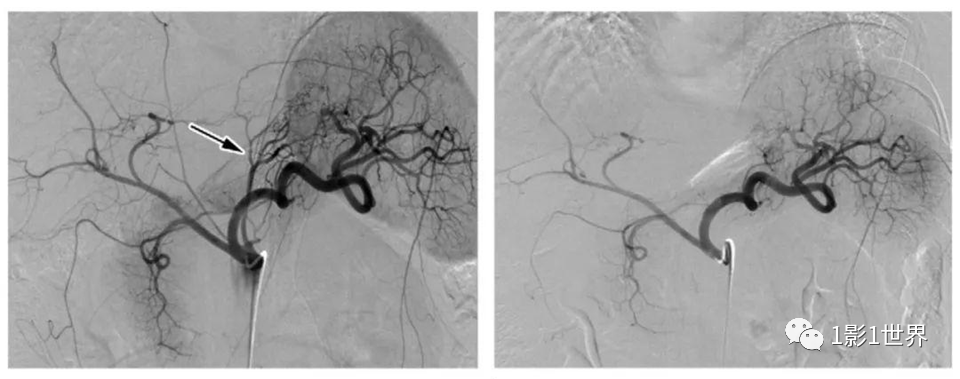

41岁妇女,体重115公斤,左图为治疗前胃左动脉(箭头),右图为栓塞治疗后

2016年滕皋军教授团队在国内开创性地开展了人体的经皮胃左动脉栓塞治疗单纯性肥胖症患者的临床研究,其中5例患者随访结果显示:经皮胃左动脉栓塞手术安全,5位患者均成功进行了栓塞手术,手术过程顺利,5位患者无一例出现胃黏膜坏死或穿孔及其他严重并发症。有效4例,有效率80%。术后6个月,5位患者平均体重减轻10.42 kg(7.58%),有2例患者减重超过15 kg;胃饥饿素下降了31.94%;腹部皮下脂肪体积减少了72.6 cm2;腰围-身高比例下降了5.75%。